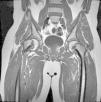

Diagnóstico por la imagenLas radiografías anteroposterior y axial de ambas caderas nos permitirán confirmar el diagnóstico. Es importante obtener la radiografía de ambas caderas por la alta incidencia de bilateralidad. En la radiografía antero-posterior y axial de ambas caderas podemos observar un desplazamiento antero-superior de la metáfisis proximal del fémur (cuello femoral) respecto a la epífisis (cabeza femoral). Denominamos signo de Steel, a la doble densidad radiográfica creada por la epífisis que se desplaza posteriormente y se superpone a la parte medial de la metáfisis (fig. 1). La línea de Klein, es una línea que se traza en la parte antero-superior del cuello femoral en la radiografía antero-posterior y que corta la epífisis. En los casos de ECF, la epífisis femoral queda por debajo de esta línea (fig. 2).

La gravedad de la ECF se mide de 2 maneras. El desplazamiento de la epífisis respecto a la metáfisis es el porcentaje de desplazamiento de la cabeza femoral respecto al cuello. Este desplazamiento puede ser leve (<33%), moderado (33–50%) y grave (>50%) (fig. 3). Aunque se utiliza de forma frecuente, presenta una gran variabilidad inter-intraobservador, además de estar influenciado por la posición del paciente. Southwick describió el ángulo epífisis-diáfisis en la radiografía anteroposterior y axial de ambas caderas. Se traza una línea a través de la superficie fisaria de la epífisis y se dibuja un ángulo recto a partir de esa línea. A continuación, se traza una línea paralela a la diáfisis del fémur. El ángulo formado por estas dos últimas líneas es la medida del desplazamiento posterior. Se resta el ángulo obtenido en la cadera sana del ángulo en la ECF, obteniendo así el grado de desplazamiento. El grado de deslizamiento se clasifica como leve (<30%), moderado (30–50%) y grave (>50%) (fig. 4).